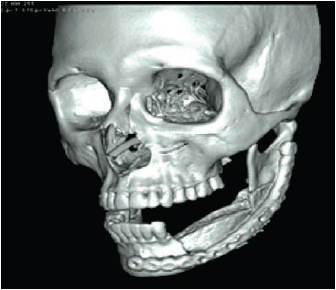

Clínicamente, se evidenciaba una deformidad en el contorno de la región del ángulo mandibular izquierdo. Intraoralmente, se observaba una lesión tumoral de 2,5 cm de alto por 2,7 cm de diámetro. Tomográficamente, estaba registrada una imagen hipodensa en la zona del segundo molar inferior izquierdo, con una expansión de cortical a vestibular y lingual ipsilateral (figuras 2 y 3). Radiográficamente, en la zona periapical del segundo molar inferior izquierdo, se observó un ensanchamiento del espacio del ligamento periodontal, sin causa aparente, con pérdida ósea perirradicular (figura 1). La paciente refirió que un año atrás, aproximadamente, se le había realizado una exodoncia del tercer molar inferior izquierdo, sin complicaciones, concomitante con el crecimiento de dicha lesión. Posterior a la evaluación, los servicios de Cirugía Plástica, Maxilofacial, Cabeza y Cuello realizaron una junta médica, donde se tomó la decisión de llevar a cabo una mandibulectomía segmentaria con reconstrucción de colgajo microvascularizado de cresta iliaca y vaciamiento ganglionar cervical ipsilateral.

La paciente estuvo hospitalizada durante ocho días después del procedimiento quirúrgico. Se le realizaron citas de control a los ocho y quince días luego del egreso del hospital, donde se evidenció un proceso infeccioso, controlado con medicación endovenosa. El 19 de mayo de 2016 tuvo control clínico e imagenológico en el que se observó una buena oseointegración del material injertado y de osteosíntesis (figura 8). Actualmente, la mujer presenta anestesia mandibular izquierda, limitación de la apertura bucal, para lo cual se indicaron terapias físicas y controles periódicos cada tres meses.